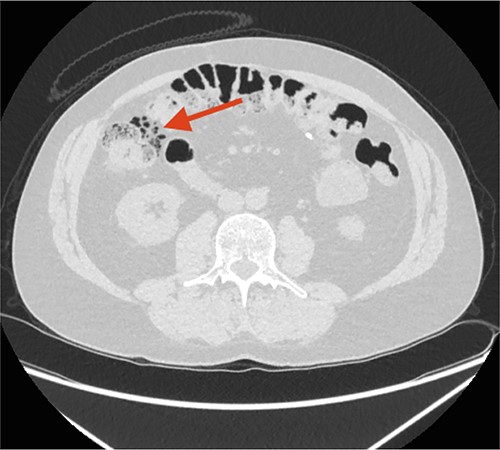

A non-contrast CT scan showed FIA located along the right colon flexure, calyceal calculi located in the left kidney and sequelae from former sigmoid colectomy with stoma formation (Fig. 1). There where no wall thickness of the colon indicating activity in the patient's Crohn's disease.

The initial CT scan. The arrow points at free intraperitoneal air (FIA) located along the right colon flexure.